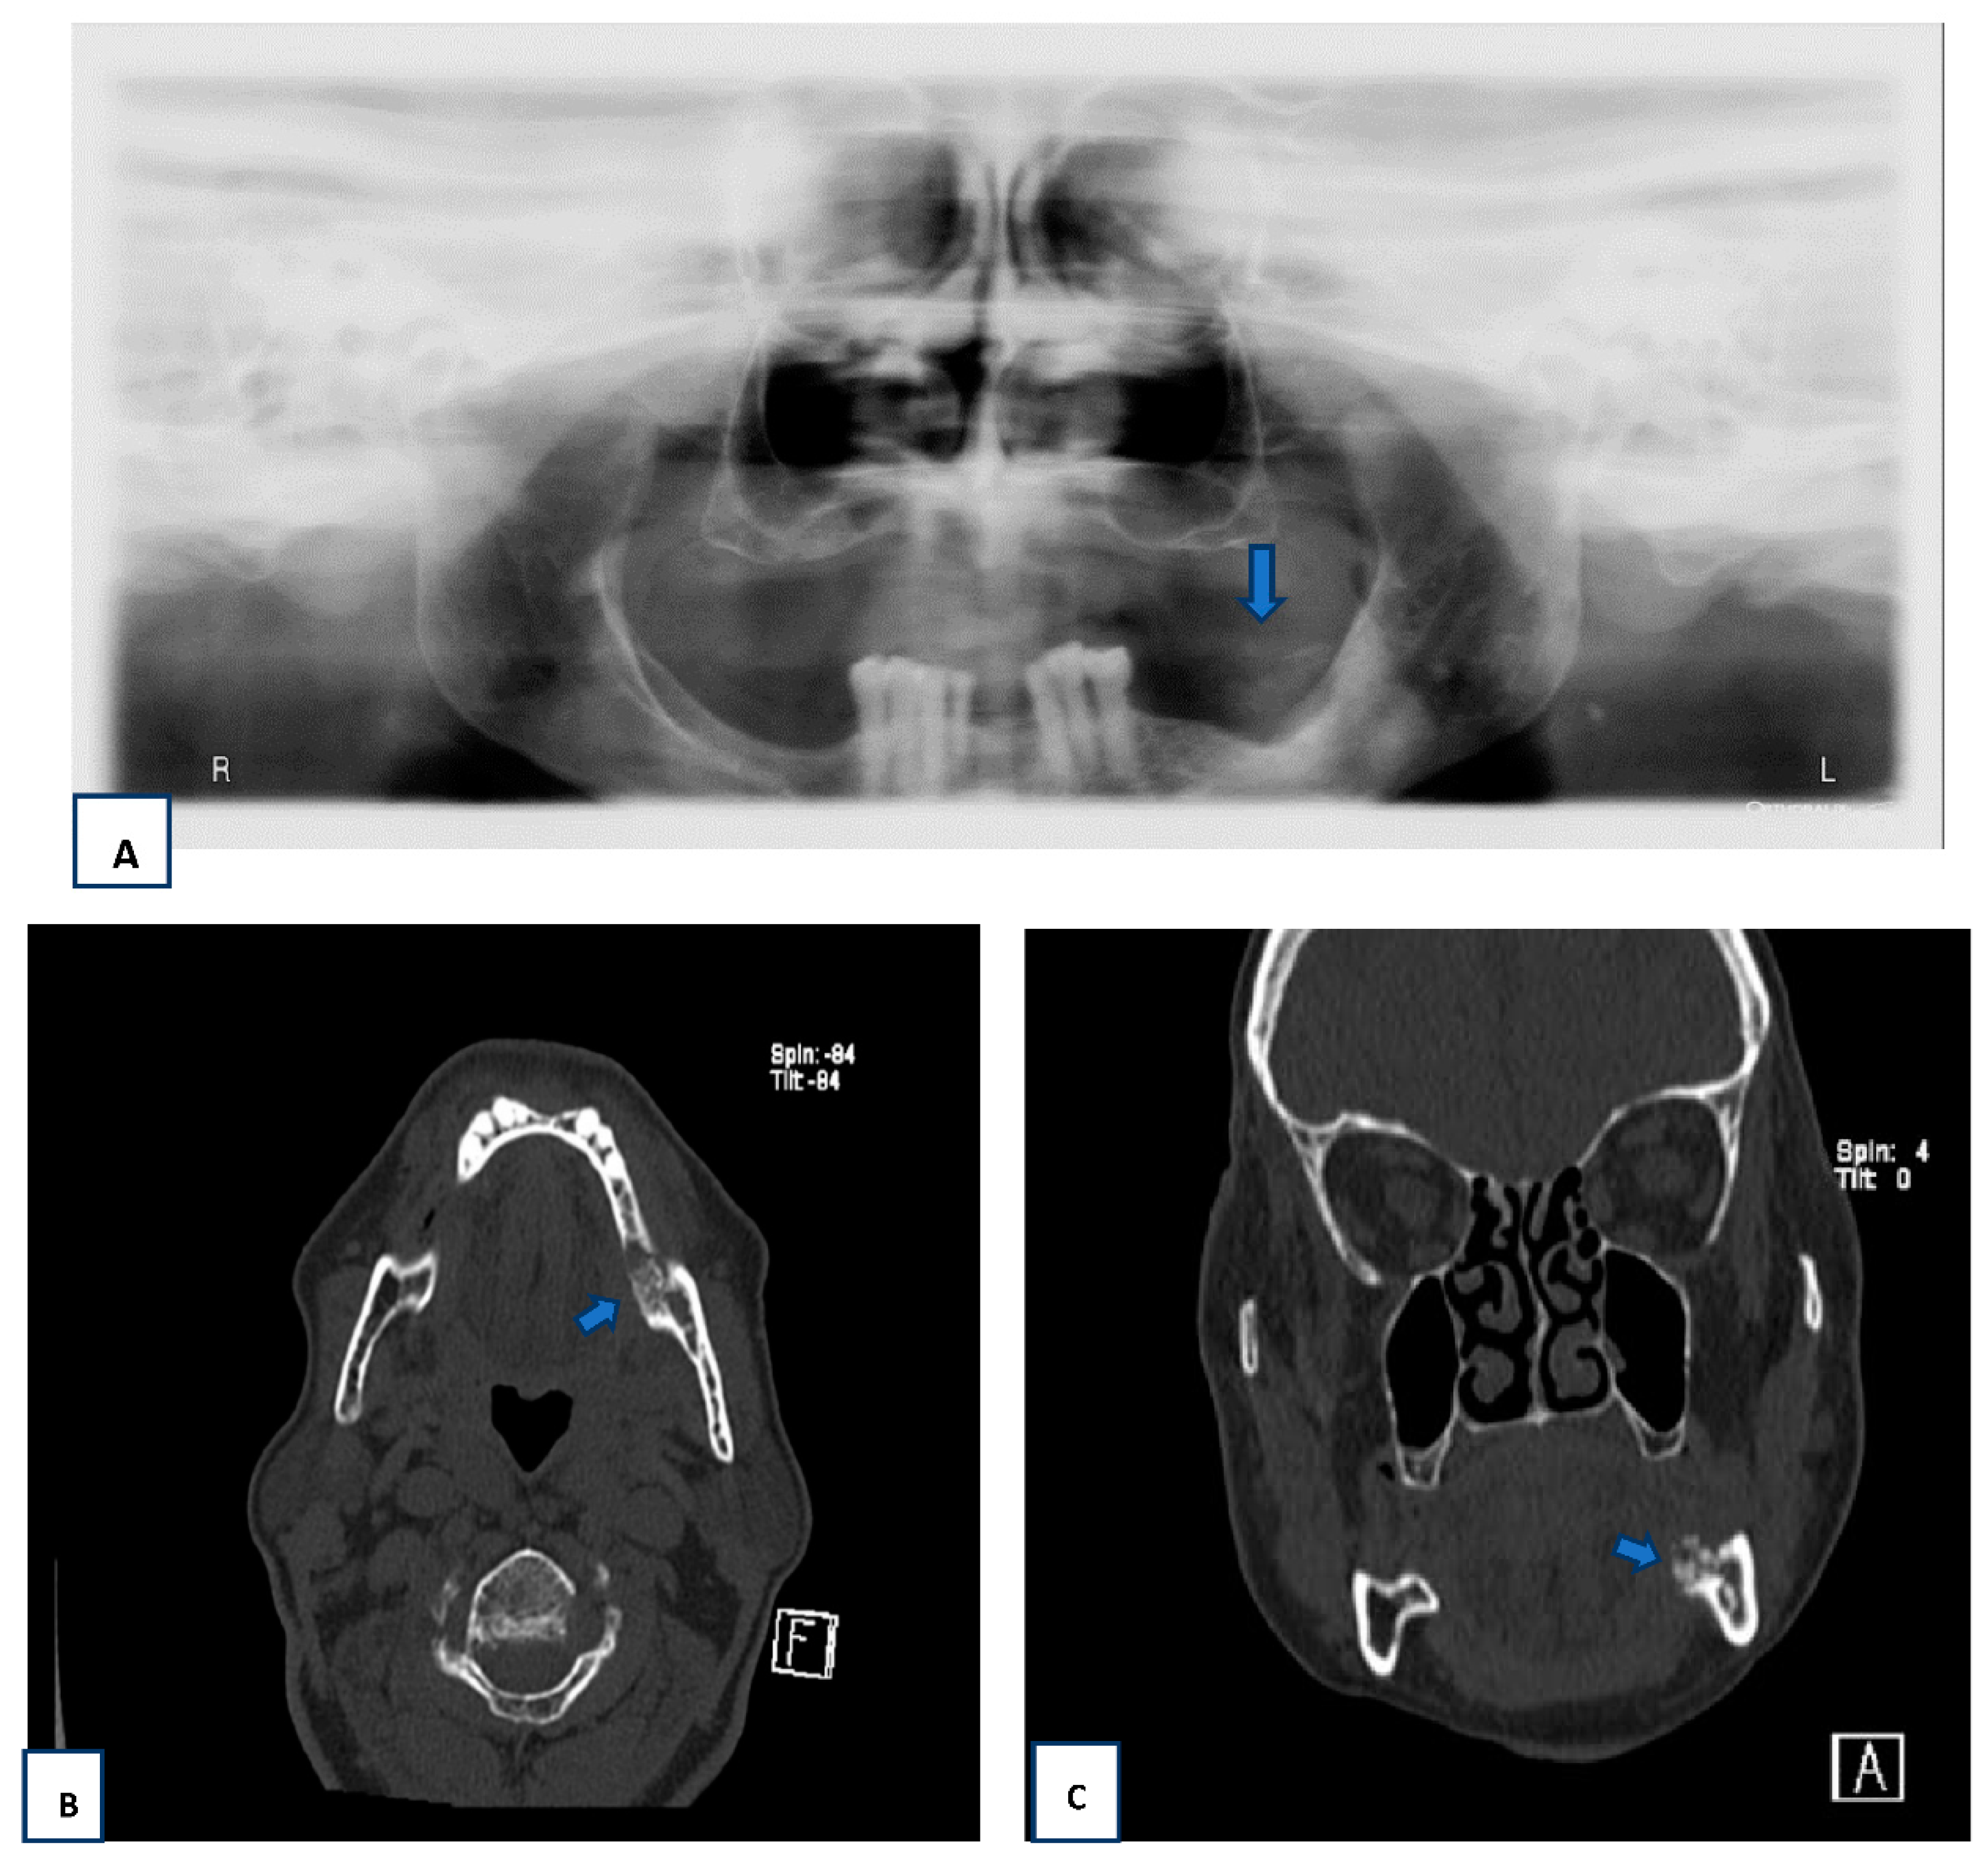

2.2. Radiographic Findings